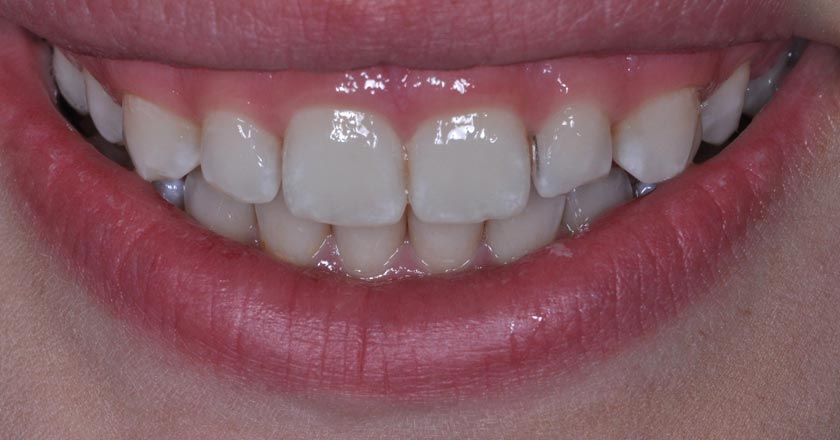

Gummy Smile - Before And After